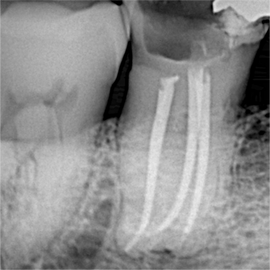

Endodontia Convencional

Retratamento Endodôntico

Além do tratamento, realizo radiografias digitais e fotografias intraorais detalhadas em todas as etapas, para que você possa acompanhar cada passo do processo.